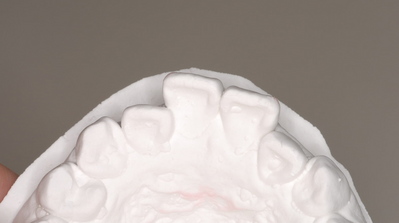

上の左右2番目の歯が内側にたおれているのをきれいにしたいという患者さんでした。

最初の状態

下から見た図